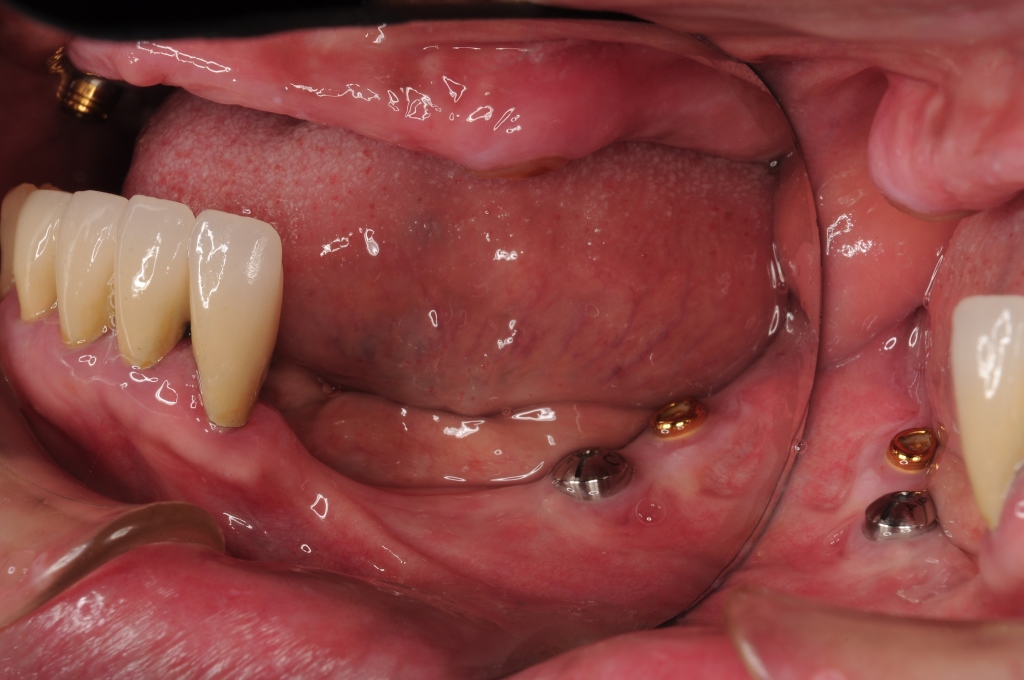

高松智恵子170626 4 宮田歯科クリニック